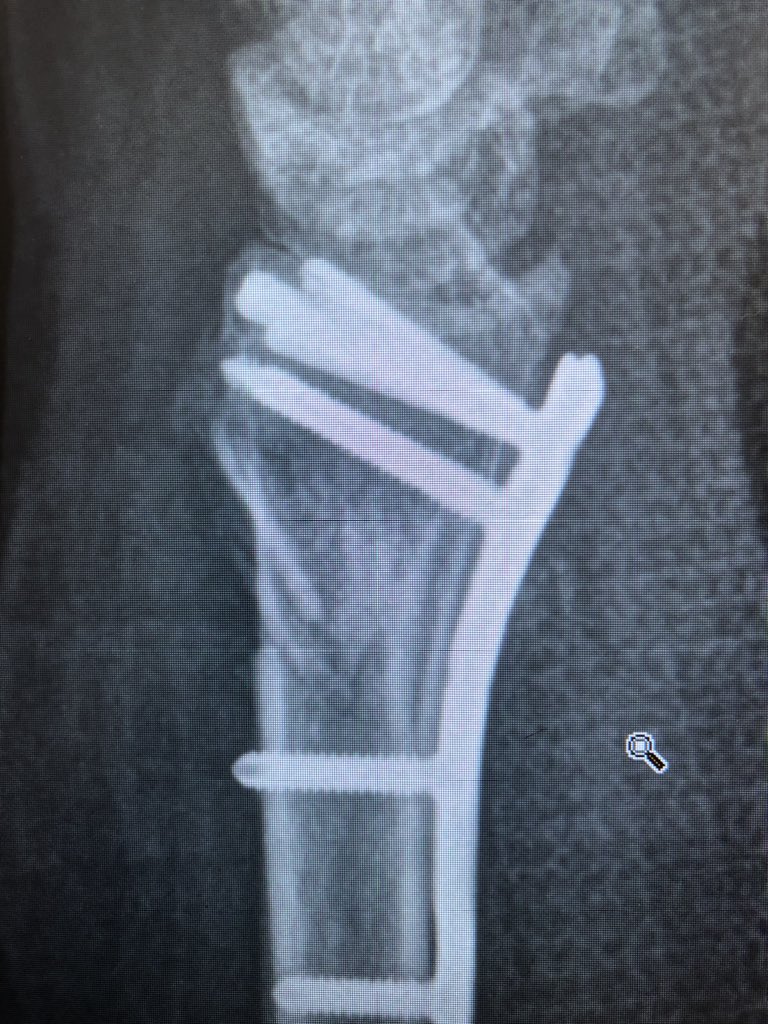

Point 1:

The proximal fragment radius spike has a risk of translational mal-reduction and this can bother rotation of the forearm.

Reduce this by putting a ‘lamina spreader’ in the inter-osseus space Before locking the shaft screws and clear the DRUJ.

Point 2:

The dorsal metaphyseal comminution. The dorsal cortex fragment is ‘fallen in’ inside the osteoporotic metaphyseal void.

I addressed this after plating finished, made a 4.5 mm drill hole in the ‘window’ of the plate to push the fragment and fill in graft substitute.

This was the patient at 2 weeks. Already on range of motion. The flat lateral X-ray always looks like the screws are in the joint. That’s because of the distal radius joint inclination angle.

Take intra-operative 20 degree elevated lateral shot to see through the joint.